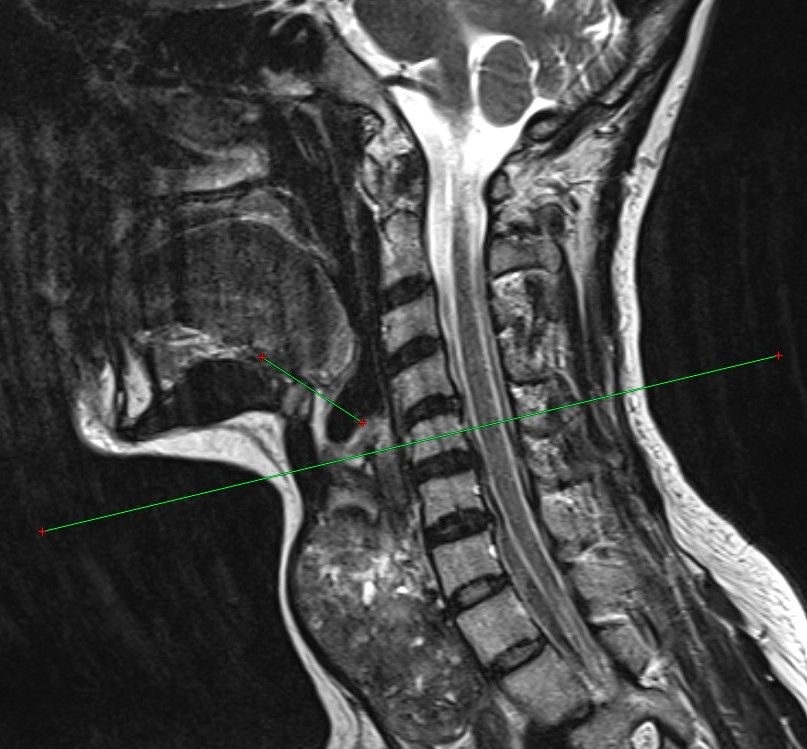

Хирургическое лечение остается основным методом борьбы с заболеваниями щитовидной железы. Существующие техники перевязки верхних полюсов ориентированы на нормальный объем органа и не учитывают анатомические изменения при его увеличении.

Новый метод позволяет точнее определять толщину и уровень расположения верхнего полюса увеличенной железы, а также снизить риск интра- и послеоперационных осложнений, таких как кровотечение и повреждение верхнего гортанного нерва.

Методика проста в применении и может быть внедрена в любом стационаре, оснащенном компьютерным томографом, отметили в Центре медиакоммуникаций Оренбургского государственного медицинского университета.